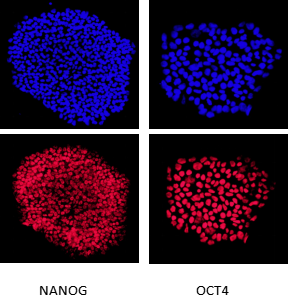

经过PCR和测序鉴定,确定获得在AAVS1位点敲入EGFP的纯合iPSC细胞系,荧光显微镜下观察到EGFP 100%表达。细胞培养后经G显带进行染色体核型分析,显示染色体数为46数目正常,染色体结构无明显异常。通过免疫荧光染色检测NANOG、OCT4和SOX2三个干性标记基因,均能检测出阳性信号,表明该敲入细胞具有干性。

图6 iPSC-EGFP免疫荧光-干性检测(通过免疫荧光染色,检测NANOG、OCT4和SOX2三个干性标记基因,均能检测出阳性信号,表明该敲入细胞具有干性)